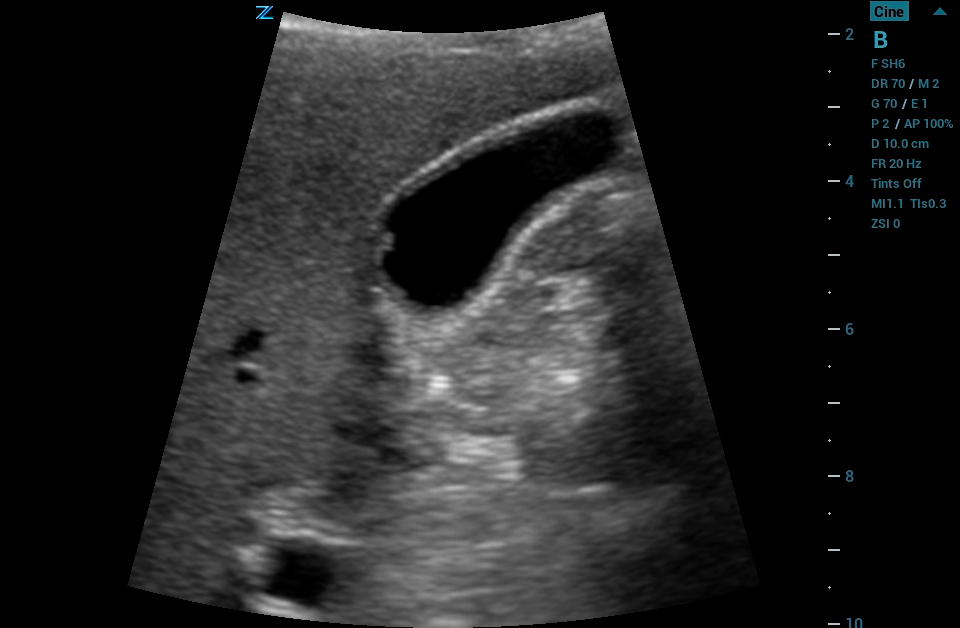

The ZS3 Ultrasound System Diamond Edition 2.0 is the ultimate imaging platform combining premium performance and mobility for today’s demanding ultrasound environments. Equipped with next generation ZONE Sonography® Technology+ (ZST+), the ZS3 System takes image clarity to new heights across a broad spectrum of body types from pediatric to bariatric. With every pixel in focus to imaging depths up to 40cm, the ZS3 System delivers unsurpassed image quality for the widest range of clinical applications.

CEUS

Contrast Enhanced Ultrasound (CEUS), Mindray’s unique approach to contrast imaging, allows clinicians to obtain the information needed with a lower dose of the contrast agent. CEUS is now available on all imaging transducers (1-20MHz).